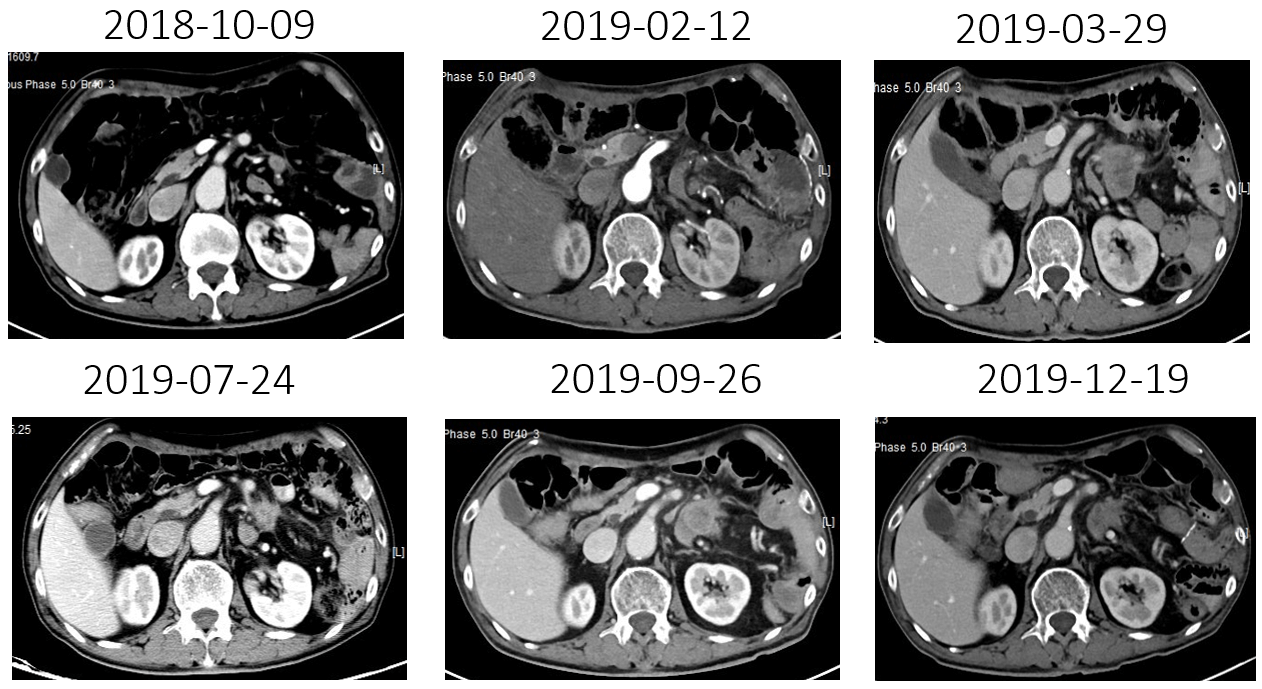

(4)2019-07-24复查CT:腹腔肿大淋巴结较放疗前缩小

(5)2019-09-26复查CT:腹腔肿大淋巴结较放疗后增大,出现左上腹痛

(9)12-19复查CT:腹腔淋巴结较09-26日缩小,3疗程“雷替曲塞 durvalumab“治疗评估达PR。